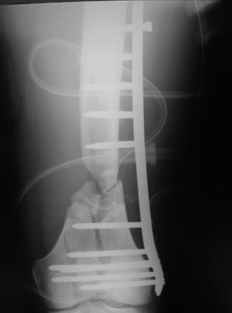

This is what we have done... As generally true for LISS look at the bone not the hardware.

There are two more srews above. The one not completely in got damaged head.